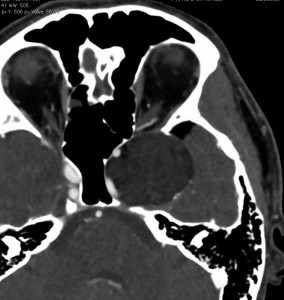

前頭蓋底類皮のう胞

蝶形骨平面から鞍結節上に発生するもので多いタイプです。左側のT2強調画像で内容物がまだらに見え,右側の拡散強調画像で高信号(白い)に見えるので診断確定です。内頸動脈や前大脳動脈や穿通枝などとの癒着が強いものが多いので剥離は難しく要注意です。ある程度の大きさを超えると経鼻内視鏡手術では摘出できません。この腫瘍は脳槽内にあるので,一回の手術でのう胞の壁も含めて全部摘出しなければなりません。そうしないと,手術後に内容物(皮脂と汗とケラチン)が髄液の中に産生されて漏れ出て,難治性の水頭症になります。